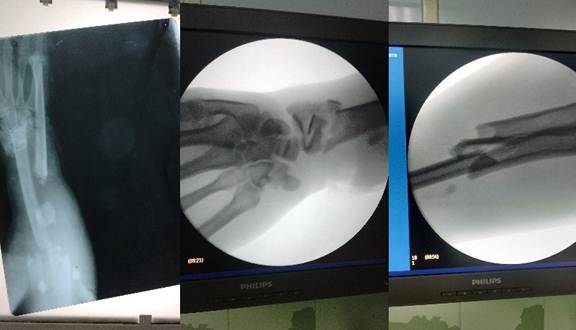

El examen radiográfico simple del antebrazo derecho en proyecciones anteroposterior y lateral mostró solución de continuidad del tejido óseo a nivel del radio distal derecho y tercio superior, lo que evidenció una fractura segmentaria abierta en su foco distal (figura 2).

La radiografía simple del tobillo izquierdo en proyecciones anteroposterior y lateral confirmó la presencia de luxación tibio-astragalina (figura 3).